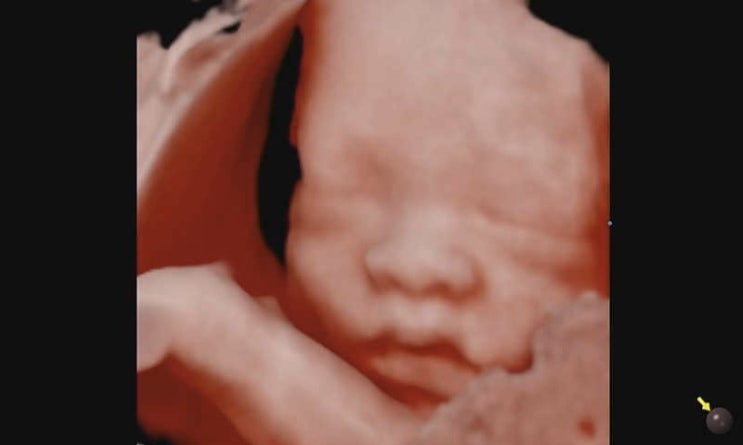

[28주 5일] 정기검진/ 입체초음파/ 출산준비

이제 임신 후기 28주에 접어들었다. 24주에 임당검사 통과하고 별다른 이벤트는 없었다. 28주에는 정기검진...